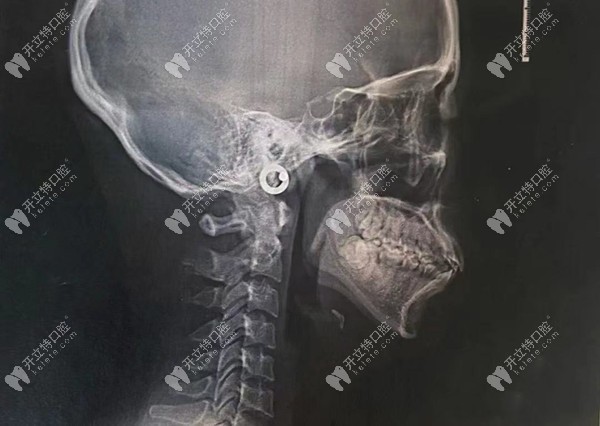

拍完CT后我的牙齒癥狀為:骨性齙牙、嘴凸、下巴后縮

方案:金屬自鎖托槽,矯正周期為兩年左右,拔4顆牙打6顆骨釘。